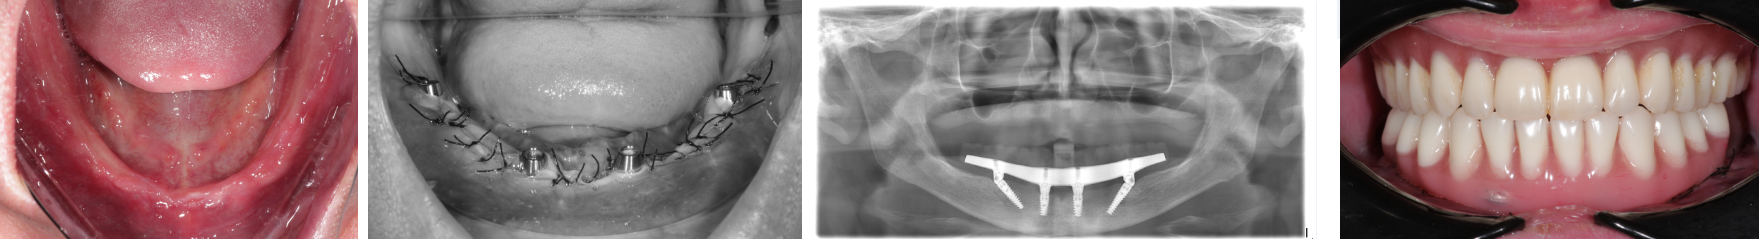

Пациент А

Пациент В

Лечение пациента по

методике All-on-4 проводится врачом

стоматологом ортопедом и врачом хирургом.

Для трехмерного планирования и

моделирования любого, отдельно взятого

случая лечения, применяется современная

компьютерная технология, создается 3D

визуализация каждого этапа лечения.

Это позволяет минимизировать погрешность

и ошибки в работе. При помощи 3D программы,

создается индивидуальный хирургический

шаблон, который позволяет планировать

и точно установить имплантаты в кость.

При помощи 3D моделирования,

конструкция для немедленной нагрузки

изготавливается до операции. Протез

можно установить в день операции или в

течении недели после нее. Временный

протезный аппарат с облегченными

искусственными коронками, с встроенной

внутренней жесткой конструкцией

стабилизирует имплантаты.

Немедленная нагрузка

важна для процесса остеоинтеграции чем

раньше кость будет получать нагрузку,

тем быстрее приживутся имплантаты.

Временный протез накладывается сроком

до 6 месяцев. Далее идет замена на

постоянную конструкцию.